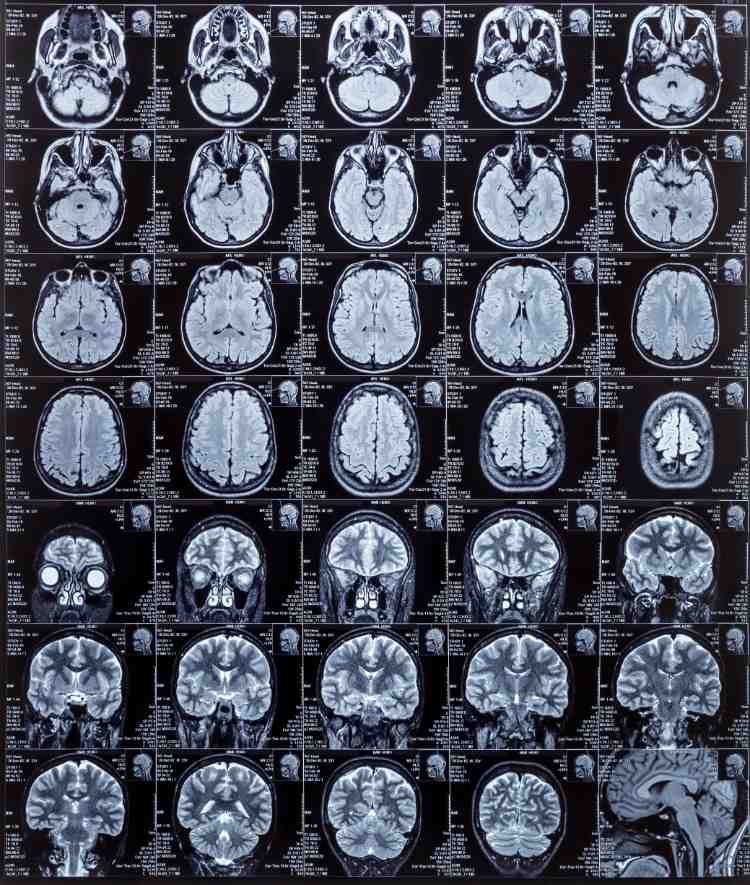

K ischemickej cievnej mozgovej príhode dôjde, keď krvná zrazenina zablokuje tepnu, ktorá dodáva krv do mozgu. To sa však môže vytvoriť aj kdekoľvek v tele a cestovať do mozgu. Hemoragická mŕtvica nastáva vtedy, ak dôjde k krvácaniu do mozgu, ktoré poškodí blízke bunky. Asi 85% mozgových príhod je ischemických a 15% hemoragických. Toto je druhá najčastejšia príčina smrti na celom svete. Hlavným zistením výskumu je, že spotreba vlákniny, ako aj ovocia a zeleniny prudko stúpla. To je spojené s nižším rizikom a v konečnom dôsledku to pomáha predchádzať ischemickej cievnej mozgovej príhode. To tiež zodpovedá súčasným európskym smerniciam. Verejnosť by preto mala byť poučená, aby zvýšila príjem vlákniny z celých zŕn a ovocia a zeleniny, ak už tieto pokyny nespĺňa.